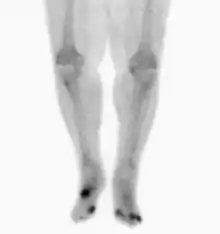

Radiographs and CT are the initial method of diagnosis, but are not sensitive and only moderately specific for the diagnosis. They can show the cortical destruction of advanced osteomyelitis, but can miss nascent or indolent diagnoses.[22]

Confirmation is most often by MRI. The presence of edema, diagnosed as increased signal on T2 sequences, is sensitive, but not specific, as edema can occur in reaction to adjacent cellulitis. Confirmation of bony marrow and cortical destruction by viewing the T1 sequences significantly increases specificity. The administration of intravenous gadolinium-based contrast enhances specificity further. In certain situations, such as severe Charcot arthropathy, diagnosis with MRI is still difficult.[22] Similarly, it is limited in distinguishing avascular necrosis from osteomyelitis in sickle cell anemia.[23]

Nuclear medicine scans can be a helpful adjunct to MRI in patients who have metallic hardware that limits or prevents effective magnetic resonance. Generally a triple phase technetium 99 based scan will show increased uptake on all three phases. Gallium scans are 100% sensitive for osteomyelitis but not specific, and may be helpful in patients with metallic prostheses. Combined WBC imaging with marrow studies has 90% accuracy in diagnosing osteomyelitis.[24]